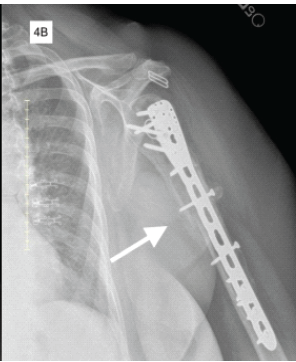

Open Reduction and Internal Fixation with Bone Morphogenetic Protein-2 for Correction of Nonunion Humeral Shaft Fracture with Pseudoarthrosis in the Geriatric Population: A Case Report

Ryan M. Tapio , Kai Zhu , David Frolov , Vadim Dolgov , Miguel Schmitz

………………………………p.124-128